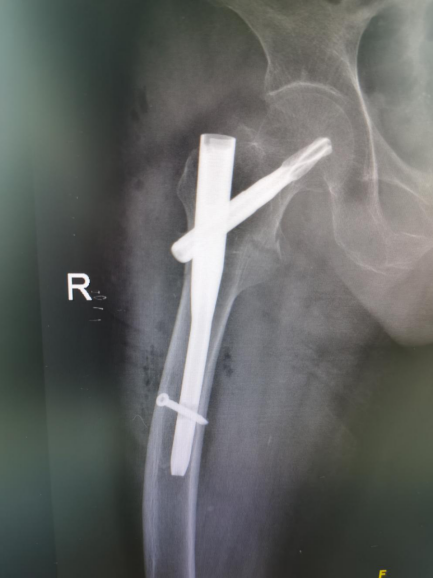

上图为术后X线,可见内固定物位置满意

手术在麻醉科徐子龙医生的严密生命体征监护下,周世峰教授带领司振兴、栾斐宇医师顺利完成,从开皮到缝合仅用时45分钟。周世峰教授利用术中C-arm透视定位,精准植入髓内固定主钉、螺旋刀片及远端锁定钉,过程顺利,通过术中的精细止血,老人出血量极少。手术结束后老人状态良好,老人翻身、坐起再也没有疼痛感。